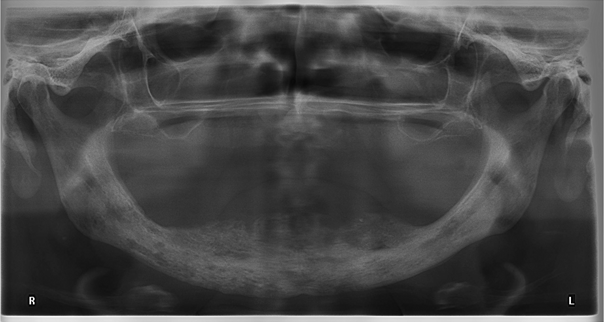

A 74-year-old edentulous woman with osteoporosis and fibromyalgia complained about growing pressure pain of the mandible following extraction of the lower anterior teeth and insertion of mucosa supported complete denture 6 months ago. Her medical history revealed 6 time administration of denosumab (Prolia® 60 mg) subcutaneously over the past 2.5 years. Fibromyalgia was treated with decortin. While intraorally no dehiscence was detected (Figure 1 [Fig. 1]), a panoramic view indicated irregular bone morphology especially in anterior mandible (Figure 2 [Fig. 2]) compared to preoperative imaging 10 months ago (Figure 3 [Fig. 3]). A CT scan illustrated the whole extent (Figure 4 [Fig. 4]). A RANK-Ligand inhibitor (denosumab) associated osteonecrosis of the mandible was diagnosed and reminded us of known BP effects on the jaw. Due to missing dehiscence she was treated conservatively with sultamicillin and prosthesis leave for 2 months with slight improvement of complaints. On the other hand with respect to the great extent of the osteonecrosis, we clarified the potential need of microvascular free flap for reconstruction.

Figure 3: Panoramic pre-extraction view with remaining anterior teeth 10 months ago

Figure 4: Finally CT scan showed up whole extent of osteonecrosis